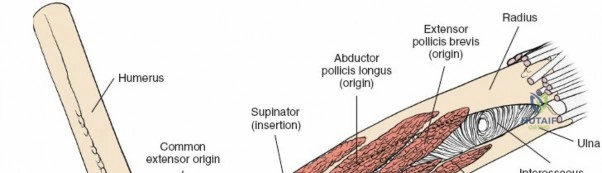

Deep Surgical Dissection: Exposing the Proximal Third

Exposing the proximal third of the radius requires extreme vigilance due to the proximity of the posterior interosseous nerve. The key anatomical landmark here is the insertion of the biceps tendon. Follow the biceps tendon distally to its insertion on the bicipital tuberosity of the radius. A small bursa lies just lateral to the tendon; incise this bursa to gain initial access to the proximal radial shaft. Because the radial artery lies superficial and medial to the tendon at this level, all deep dissection must remain strictly lateral to the biceps tendon.

The proximal radius is draped by the supinator muscle. The PIN passes directly through the belly of the supinator. To protect the nerve, the forearm must be fully supinated. Supination dynamically rotates the radius, carrying the insertion of the supinator anteriorly and simultaneously displacing the PIN laterally and posteriorly, safely away from the surgical field.

With the forearm fully supinated, identify the broad insertion of the supinator on the anterior aspect of the radius. Incise the supinator directly along the line of its insertion onto the bone. It is critical to detach the muscle by dividing its insertion sharply at the bone, rather than splitting the muscle belly, which would risk cutting the PIN.

Proceed with strict subperiosteal dissection, elevating the supinator laterally off the bone. This is one of the rare instances in orthopedic surgery where the safety gained by staying in a subperiosteal plane completely outweighs the theoretical vascular damage to the bone caused by periosteal stripping. The elevated supinator muscle belly now acts as a protective cushion for the PIN.